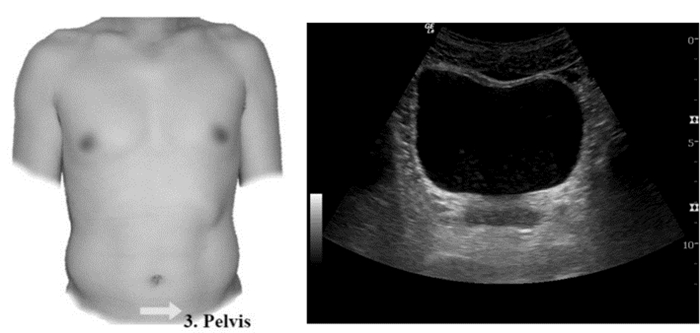

3.1.3 创伤的超声诊断的步骤及流程(1)创伤的超声诊断步骤:创伤患者床旁超声检查至少5个部位:①右上腹,也叫肝周切面、莫里森窝切面或右上1/4切面。如出现无回声区提示腹腔内出血(图 22-23)。②左上腹脾肾间隙,如出现无回声区亦提示腹腔内出血(图 24-25);③耻骨上/盆腔切面,如显示膀胱后或子宫后无回声区,提示盆腔出血可能(图 26-27);④剑突下切面,常用于探查心包有无无回声区(图 28),具体心包积液征象见2.1.2 常见异常超声心动声像图。⑤肺部超声,主要用于探查有无血气胸、肋骨骨折,具体征象见2.2肺超声。

| 图 26 耻骨上/盆腔探查部位及正常超声影像 |

| 图 27 盆腔出现无回声区 |